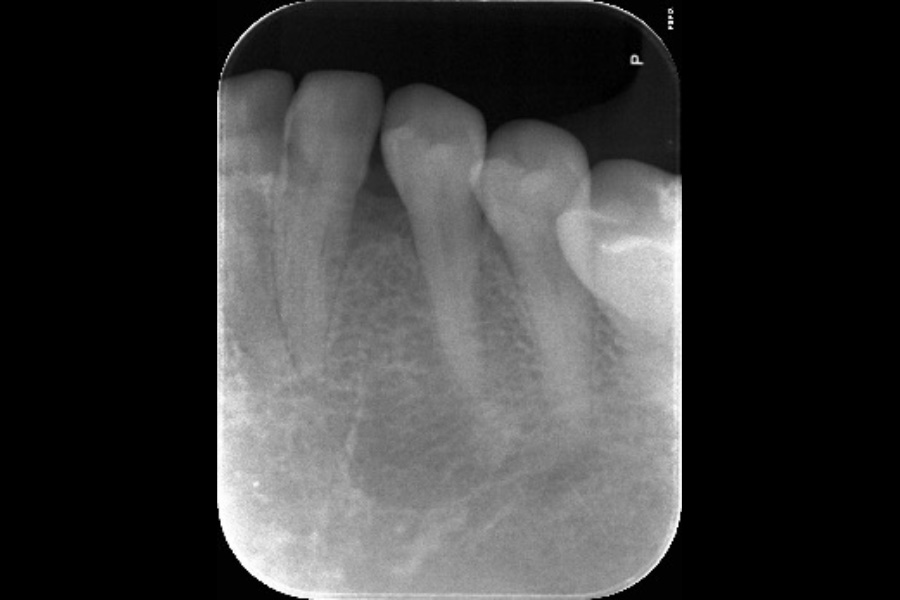

右下奥歯の歯ぐきから出血する

【歯周組織再生療法】

- 主訴

- 右下奥歯の歯ぐきから出血する

- 治療内容

- 右下4遠心に垂直性骨吸収が認められたためエムドゲインと骨補填材を用いて歯周組織再生療法を行った

- 治療に伴うリスク

- 歯肉退縮、知覚過敏